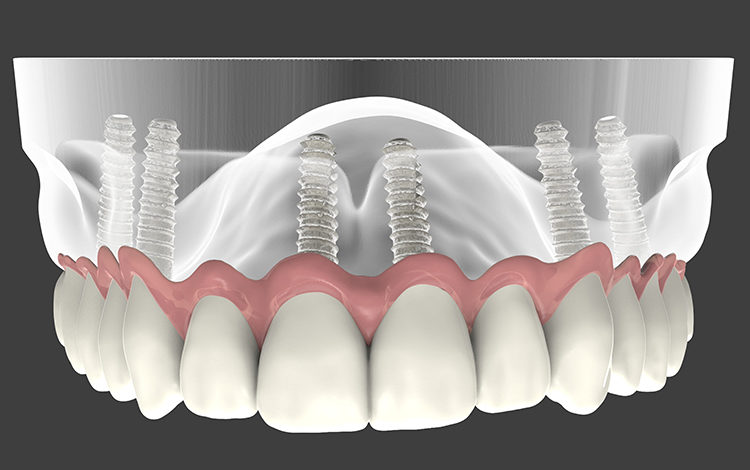

Diş implantları, eksik dişlerin tamamlandığı ve beraberinde estetik bir görünümün elde edildiği doğala en yakın uygulamadır. Diş hekiminiz, kırık veya eksik dişlerin yerine konulması için size en iyi çözümü sunar. Çünkü, şimdi ve gelecekte en konforlu diş tedavisinin sağlığının tadını çıkarmanızı ve özgürce gülümsemenizi istiyoruz.

Diş İmplantları doku ile uyumlu son derece ufak ve uzmanı tarafından yapıldığında sizlere hiç sorun çıkartamayacak titanyum vidalardır. Bundan 10 yıl öncesine kadar bazı sistemik hastalıkları olanlarda sınırlı kullanımı varken günümüzde Zirkotitan ve Akıllı Hidrofilik İmplant teknolojisi ile kullanım sınırlamaları oldukça azalmaıştır.

Yaşınız kaç olursa olsun, eğer sağlıklı bir çene kemiğiniz varsa implant sizin için en doğru seçenek olabilir.